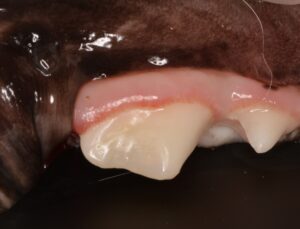

右側:コンポジットレジンで修復

露髄していない右側は幸いレントゲン上で感染を示す所はありませんでした。

しかし象牙質が露出しており、このままでは細菌が入り込み、後から感染を起こす可能性があるため、コンポジットレジンで修復を行いました。